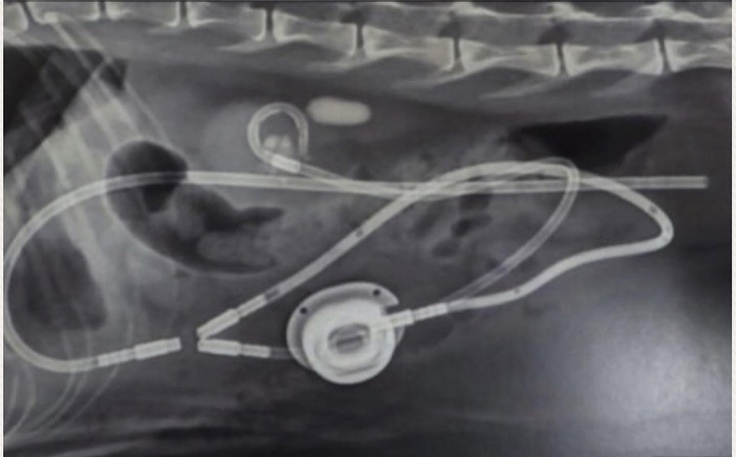

お腹のポート😿

最近では珍しくツナちゃんのへそ天が見られたので、写真を撮って見たら、お腹にポートが入ってるのがよく分かりました、。

写真のぷっくり膨らんでいるところが、SUBシステムのポートという部分であり、腎臓のカテーテルと膀胱のカテーテルを繋ぐ役割をしている"金属製の器具"です。

メンテナンス時にはここに注射をさしたり、SUBシステムがきちんと機能しているか確かめたり、シュウ酸カルシウムなどで詰まらないよう洗浄したりします。その度に麻酔もされます。

レントゲンを見ると、ツナちゃんの体の中に、こんなに大きな器具が入っているのだと実感します。

もし自分の体の中にこんなものが入っていたらと考えると、怖くなると同時に、ツナちゃんは相当な違和感と毎日闘っているのだと思うと、見守ることしかできない事が、本当に辛いです。。